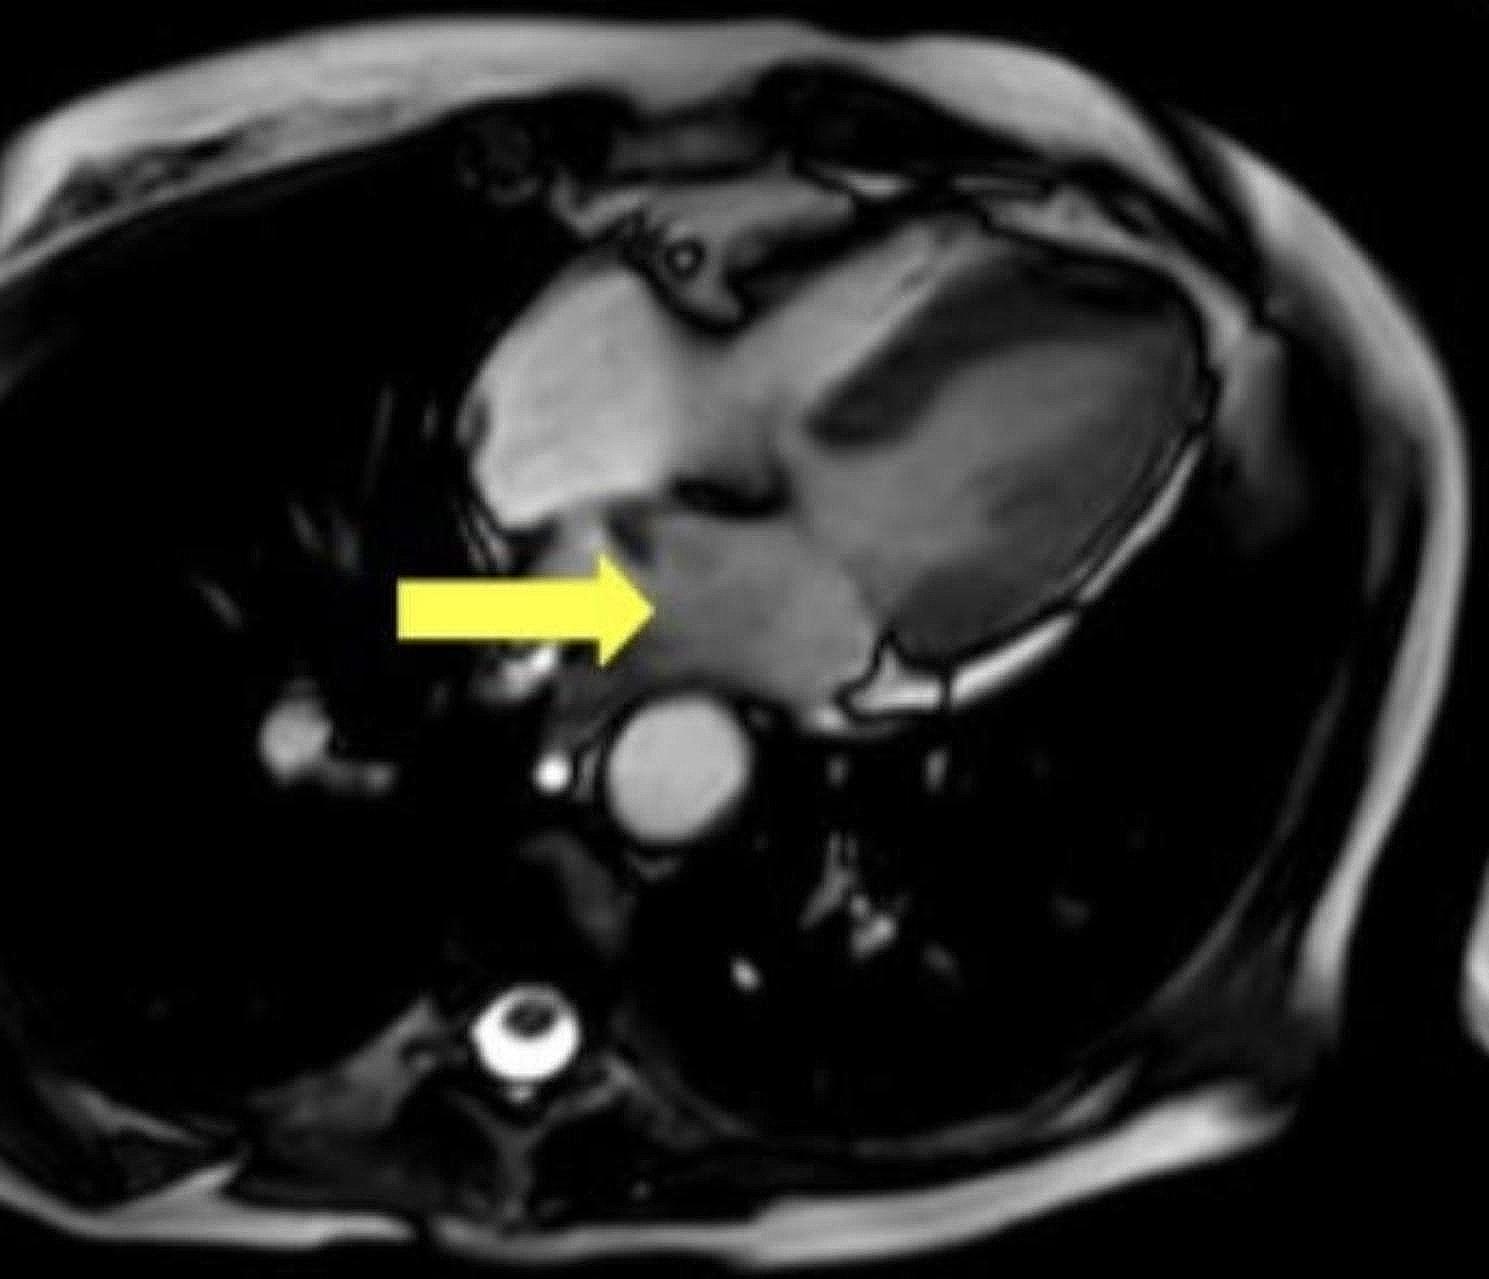

Atrial myxomas are typically found in the left atrium and are the most common among overall rare cardiac tumors. Herein, we describe the clinical course of a 72-year-old female with non-small cell lung adenocarcinoma found to have an atrial mass during an imaging for evaluation for lung cancer progression. Differentiating between distinct types of masses can pose a challenge to the treatment team especially in the setting of exiting malignancy. This case demonstrates the complex decision making involved in the diagnosis, and timing of intervention to remove atrial mass in patients with frailty and a fast-growing cardiac mass.

心房黏液瘤通常位于左心房,是总体罕见心脏肿瘤中最常见的类型。在此,我们描述了一名72岁女性非小细胞肺腺癌患者的临床病程,该患者在评估肺癌进展的影像学检查中发现有心房肿物。区分不同类型的肿物对治疗团队来说可能是一项挑战,尤其是在存在恶性肿瘤的情况下。本病例展示了在诊断以及对体弱且心脏肿物生长迅速的患者进行心房肿物切除干预时机方面所涉及的复杂决策。